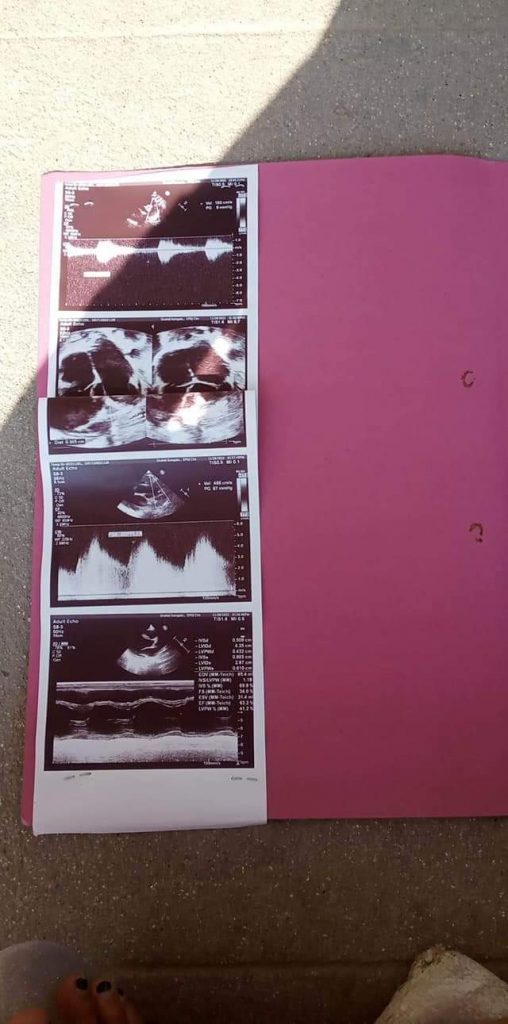

“झापा र विराटनगर अस्पतालहरुमा देखाएँ, उपचार हुन सम्भव भएन”, उहाँले भन्नुभयो, “मुटुमा प्वाल रहेको थाहा पाएपछि डाक्टरको सल्लाह अनुसार शहिद गंगालाल हृदय केन्द्रमा उपचार गराइरहेको छु ।” आफ्नो आर्थिक अवस्था कमजोर रहेकाले उपचारमा समस्या परेको उहाँको भनाइ छ ।

हालसम्म उपचारका क्रममा रू ५० हजार खर्च भएको उहाँले बताउनुभयो । उपचारका लागि करिब रू दुई लाख ५० हजार लाग्ने उपचारमा संलग्न चिकित्सकले जनाएको उहाँले बताउनुभयो । “अस्पतालमा बेड खाली नभएरका पुस ४ गते भर्ना गर्ने र पुस ६ गते शल्यक्रिया गर्ने तयारी भइरहेको छ”, उहाँले भन्नुभयो, “त्यतिबेलासम्म कोठैमा राखेर उपचार गरिरहेका छौं, आर्थिक अवस्था कमजोर भएकाले मनकारीहरुबाट सहयोग पाउने अपेक्षा गरेका छौं ।” आर्थिक अवस्था नाजुक भएकाले नै बाध्य भएर आफूले सहयोगको अपिल गरेको उहाँको भनाइ छ ।